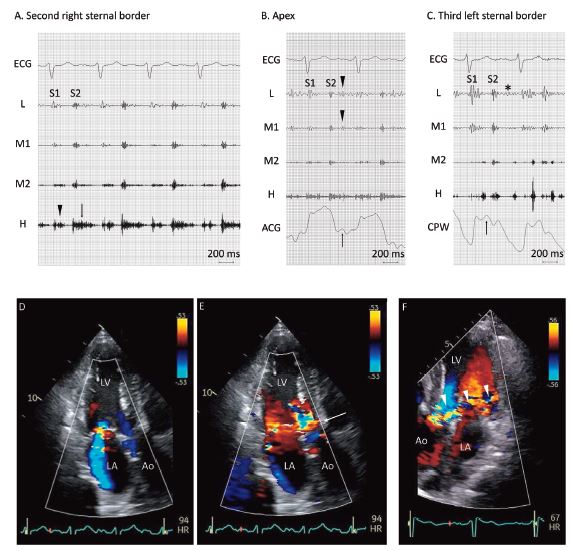

A 79-year-old man presented with a 11-day history of dyspnea. His blood pressure was 149/61 mmHg, his pulse rate was 95 beats per minute, and his oxygen saturation level was 95% while breathing ambient air. The jugular venous pulsation was elevated to 20 cm H2O. Cardiac auscultation showed a systolic ejection murmur and an early diastolic murmur (i.e., a to-and-fro murmur) at the second sternal border (Figure 1A) and gallops at the apex (Figure 1B). Phonomechanocardiography showed a diastolic rumble, along with pulsus bisferiens, at the third sternal border (Figure 1C), all these findings consistent with acute severe aortic regurgitation (AR).

Transthoracic echocardiography revealed mitral regurgitation (MR) (Figure 1D) and AR (Figure 1E, arrow); MR was considered more predominant than AR. A diagnosis of decompensated heart failure with valvular heart disease was made.

Follow-up transthoracic echocardiography after treatment or one week after admission showed severe AR throughout diastole (Figure 1F), with improvement in MR severity. The cause of acute AR was considered to be cusp bending of the right coronary cusp, which was confirmed by transesophageal echocardiography.

Figure 1: Phonocardiography on admission shows a high-pitched systolic ejection murmur (A, arrowhead) and an early- to mid-diastolic murmur (A, arrow) at the second right sternal border; note that the diastolic murmur starts immediately after the second sound (S2) and ends approximately 100 ms before the first sound (S1). At the apex, an additional low-pitched sound in early diastole (B, arrowheads) coincides with the rapid filling wave (B, arrow) of the apex cardiogram (ACG), findings consistent with the third sound. The carotid pulse wave (CPW) shows a biphasic pulse during systole, i.e., pulsus bisferiens (C, arrow), along with a diastolic rumble (C, asterisk). An apical three-chamber view of transthoracic echocardiography shows mitral regurgitation during systole (D). Note a flash of mosaic pattern in early diastole (E, arrow), in the absence of clear regurgitant flow. One week after admission, follow-up echocardiography shows severe aortic regurgitation throughout diastole (F, arrowheads). Ao denotes aorta; ECG: electrocardiography; H: high frequency; L: low frequency; LA: left atrium; LV: left ventricle; M1: lower-middle frequency; M2: higher-middle frequency.